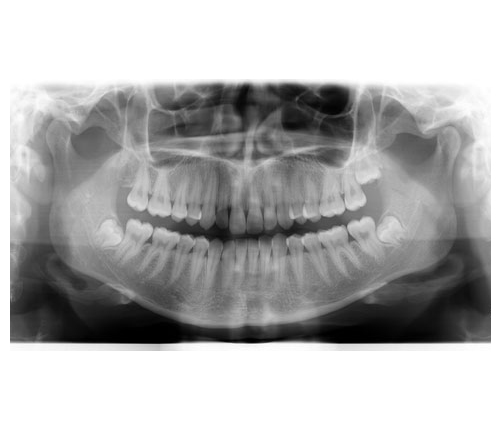

Maintaining proper nutrition and regular dental visits are proactive ways to detect health issues before they progress. By capturing images of the upper and lower jaw, a panoramic x-ray can discover bone abnormalities, TMD, jaw tumors, cysts or trauma, fractures or impacted teeth, and lead to effective diagnosis and treatment of bone and gum disease, oral cancers, and joint or sinus deformities. Grethe Jonasson, researcher at the Research Centre of the Public Dental Service in Västra Götaland initiated the fractures study, called “A prospective study of mandibular trabecular bone to predict fracture incidence in women: A low-cost screening tool in the dental clinic.” Jonasson explained, “Dental x-rays contain lots of information on bone structure. By analyzing these images, dentists can identify people who are at greater risk of fractures long before the first fracture occurs.” New pans from Gendex—the GXDP-700 and GXDP-300 provide practitioners with clear, sharp scans to advance diagnostic capabilities. While many factors affect bone density and the condition of the dentition, panoramic imaging is an effective way for dentists to monitor patients’ quality of life and make constructive recommendations for better dental health well into their senior years.